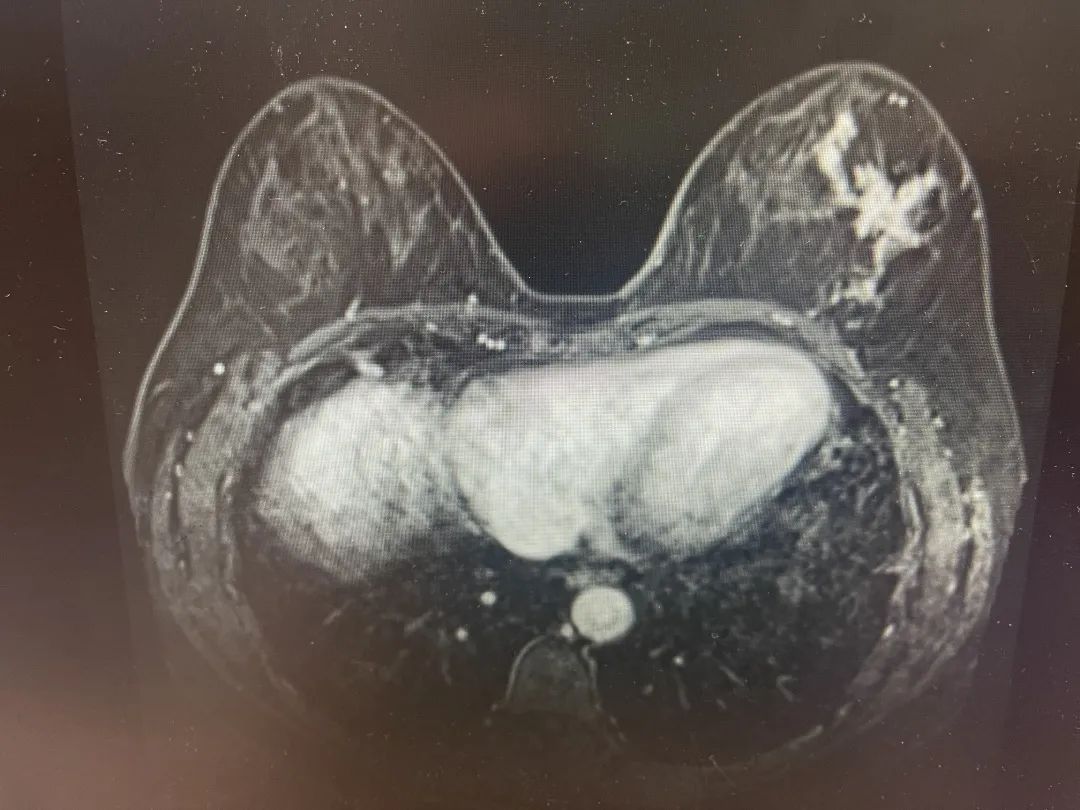

最近,乳腺外科团队顺利完成了疫情后的第一例乳房假体重建术。该患者为一位55岁中年女性,术前乳腺影像学检查(乳腺超声、乳腺钼靶X线摄片、乳腺磁共振增强)显示左乳异常病变范围广泛。跟患者术前谈话,谈到可能要切除左侧乳房,无法保留。患者表示了对自己身体完整性的强烈要求,要求尽可能保留乳房或乳房重建。

在乳房体积较大的患者,皮下腺体切除术需和乳房再造相结合,才有可能实现双侧乳房的对称。患者乳房容积较大,重建需要相当的容量,如何选择重建方式是个难题,自体背阔肌复合组织瓣是一种选择,但是患者幼年时有脊柱结核手术史,胸背部的肌肉组织和筋膜组织存在一定程度的破坏和粘连,造成组织量的缺失及手术的不确定性。假体组织可以提供足够的容量,但亦有自然性稍逊和包膜挛缩等远期不确定性,同时患者皮下脂肪极薄,术后有一定假体外露可能。

最终,全面评估患者影像学,病理学以及整体组织容量和局部脂肪厚度等情况,决定为患者施行保留乳头乳晕乳腺切除术+假体联合补片及背阔肌组织瓣的胸肌前平面乳房重建术。该术式可以使乳房动感更真实,同时背阔肌和胸大肌形成的囊袋以及补片双重保护下提高了手术的安全性,也避免了该患者单纯背阔肌自体容量的不确定性,同时在原背部手术部位切取背阔肌组织,亦不会增加其切口数量。